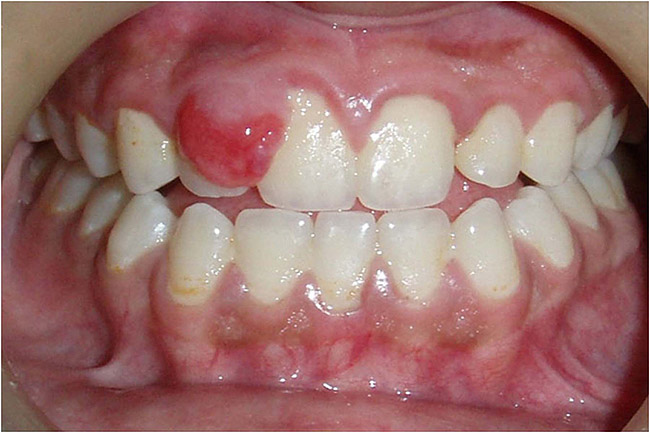

Il existe une autre forme de maladie des gencives pendant la grossesse appelée granulome pyogénique

Les femmes enceintes peuvent développer un granulome pyogénique de la grossesse, généralement après le troisième mois.

Au fur et à mesure que la grossesse avance, la probabilité de développer une tumeur semble augmenter.

Votre granulome pyogénique va-t-il disparaître naturellement ?

Étant donné que les granulomes pyogéniques proviennent souvent de changements hormonaux pendant la grossesse, votre médecin peut vous conseiller d'attendre la fin de la grossesse pour voir s'ils disparaissent d'eux-mêmes. Sinon, la chirurgie devra l'enlever. C'est un traitement chirurgical mineur car indolore, sans souci. cela peut être fait par un dentiste généraliste ou un chirurgien buccal.